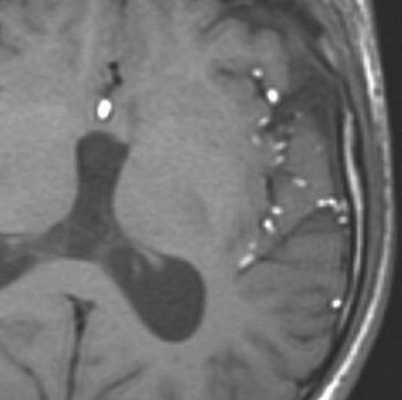

При МРТ головного мозга картина неспецифическая и зависит от содержимого кисты. Если она не содержит жира, то имеет ликворную интенсивность сигнала . В таком случае эпидермоидная киста трудно отличима от арахноидальной, хотя, как правило, не столь однородная. На МРТ типа FLAIR и диффузионно-взвешенных МРТ изображениях содержимое эпидермоидов светлее ликворного. Жировое содержимое, такие эпидермоиды еще называют холестеатомой, приводит к высокому сигналу на Т1-взвешенных МРТ головного мозга. Видимо, он обусловлен липидами, но не холестеролом. На Т2-взвешенных МРТ головного мозга он менее интенсивен чем ликвор. Контуры эпидермоидов всегда четкие. Холестеатомы составляют всего 3-5% от эпидермоидов. В 15-20% случаев встречается кальцификация по переферии кисты. Редко наблюдается контрастирование стенок.

МРТ головного мозга. Т1-взвешенные корональная и сагиттальная МРТ. Эпидермоидная киста левой височной доли.

При МРТ головного мозга картина неспецифическая и зависит от содержимого кисты. Если она не содержит жира, топри МРТ головного мозга эпидермоидная киста имеет ликворную интенсивность сигнала. В таком случае эпидермоидная киста трудно отличима от арахноидальной, хотя, как правило, не столь однородная. На FLAIR томограммах и диффузионно-взвешенных МРТ головного мозга содержимое эпидермоидов светлее ликворного. Жировое содержимое, такие эпидермоиды еще называют холестеатомой, приводит к высокому сигналу на Т1-зависимых МРТ головного мозга. Видимо, он обусловлен липидами, но не холестеролом. На Т2-взвешенных МРТ головного мозга он менее интенсивен чем ликвор. Контуры эпидермоидов на МРТ всегда четкие. Холестеатомы составляют всего 3-5% от эпидермоидов. В 15-20% случаев встречается кальцификация по переферии кисты. Редко наблюдается усиление стенок кисты при МРТ головного мозга с контрастированием.